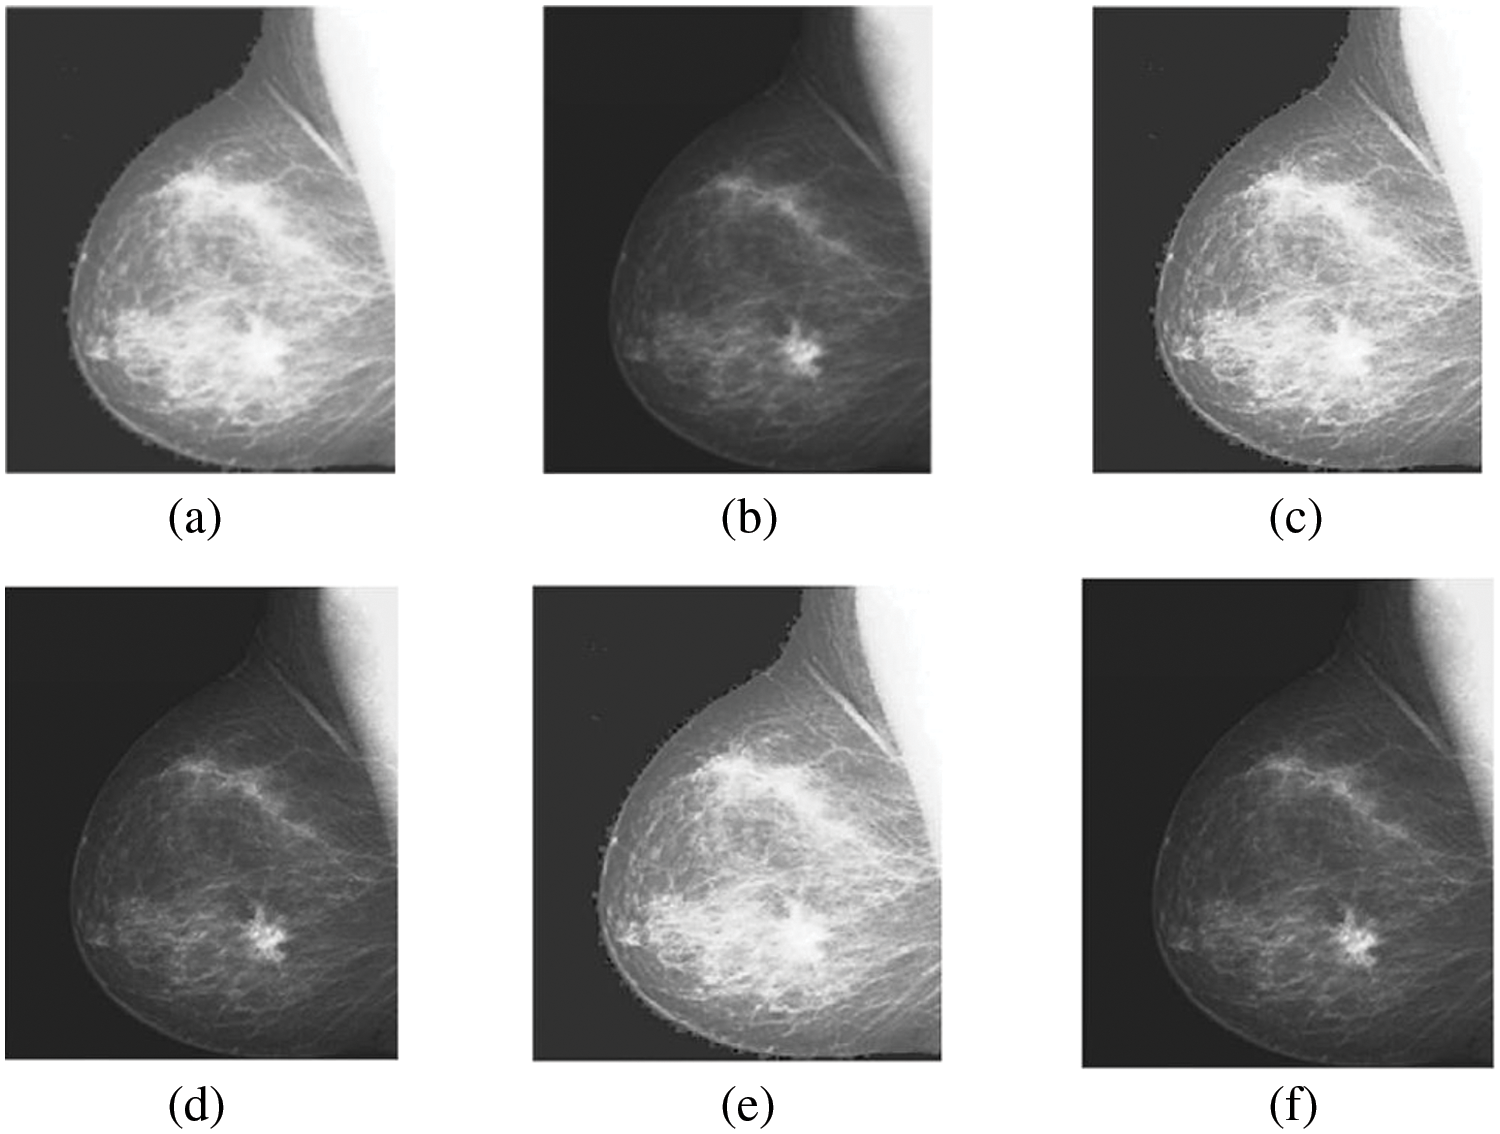

This section evaluates the effectiveness and accuracy of the novel algorithm for multi-modality medical images, specifically focusing on brain lesions and breast images. The algorithm aims to enhance the images and sharpen the edges to improve small details before performing the fusion process. The evaluation was conducted using three pairs of CT and MRI images, obtained from the website “https://sites.google.com/site/aacruzr/image-datasets” (accessed on 06/03/2024). The image sets had dimensions of 258 × 258 for sets 1 and 2, and 385 × 460 for set 3. The evaluation of the algorithm was carried out both visually and statistically [29].

Figs. 4–11 display the original CT and MRI images along with their corresponding enhanced images obtained through the proposed sharpening technique, including Unsharp masking and LF+DFT Sharpen. The enhanced images effectively highlight and enhance minor details, making them clearer and more perceptible. These enhanced images play a crucial role in subsequent stages of the fusion process, where the aim is to integrate the essential information from both CT and MRI modalities.

Figure 10: The sharpened results of “Breast CT, and MRI Image set 3” (a, b) are two source images CT and MRI, respectively, (c, d) are sharpen images by unsharp masking and (e, f) LF+DFT sharpened images

Figs. 4–11 present the fused images obtained from both existing and proposed hybrid approaches. The existing approaches, including PCA, MF, DWT, DTCWT, DCHWT and SWT, initially fuse the source images. Then, the SWT method is combined with the proposed sharpening techniques and applied to fuse the sharpened images. Comparatively, the fused images generated by the proposed methods, namely SWT+Unsharp masking and SWT+(LF+DFT), exhibit significant improvements compared to the baseline techniques. To highlight the differences among the fused images and facilitate a better understanding of the enhanced and informative nature of the images, specific areas are marked with red and green boxes in Figs. 3–10. Furthermore, a magnified version of the region marked with the red box is provided in Figs. 5 and 9 to further illustrate the qualitative analysis of brain datasets.